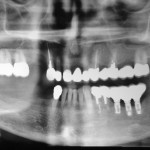

Prevenzione e trattamento dell’atrofia ossea a fini implantari: una serie di casi clinici

Riassunto

Attraverso alcuni casi esemplificativi vengono presentate le principali tecniche

di ricostruzione ossea oggi in uso per la il trattamento di difetti localizzati

del processo alveolare. Viene...